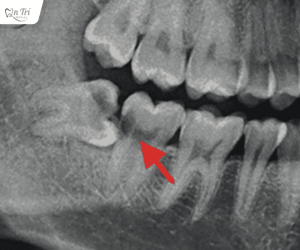

Cảnh báo nguy hiểm: Răng khôn mọc kẹt gây u nang răng

Bài viết được cố vấn chuyên môn bởi BS Trịnh Quang Trí Răng khôn mọc kẹt...